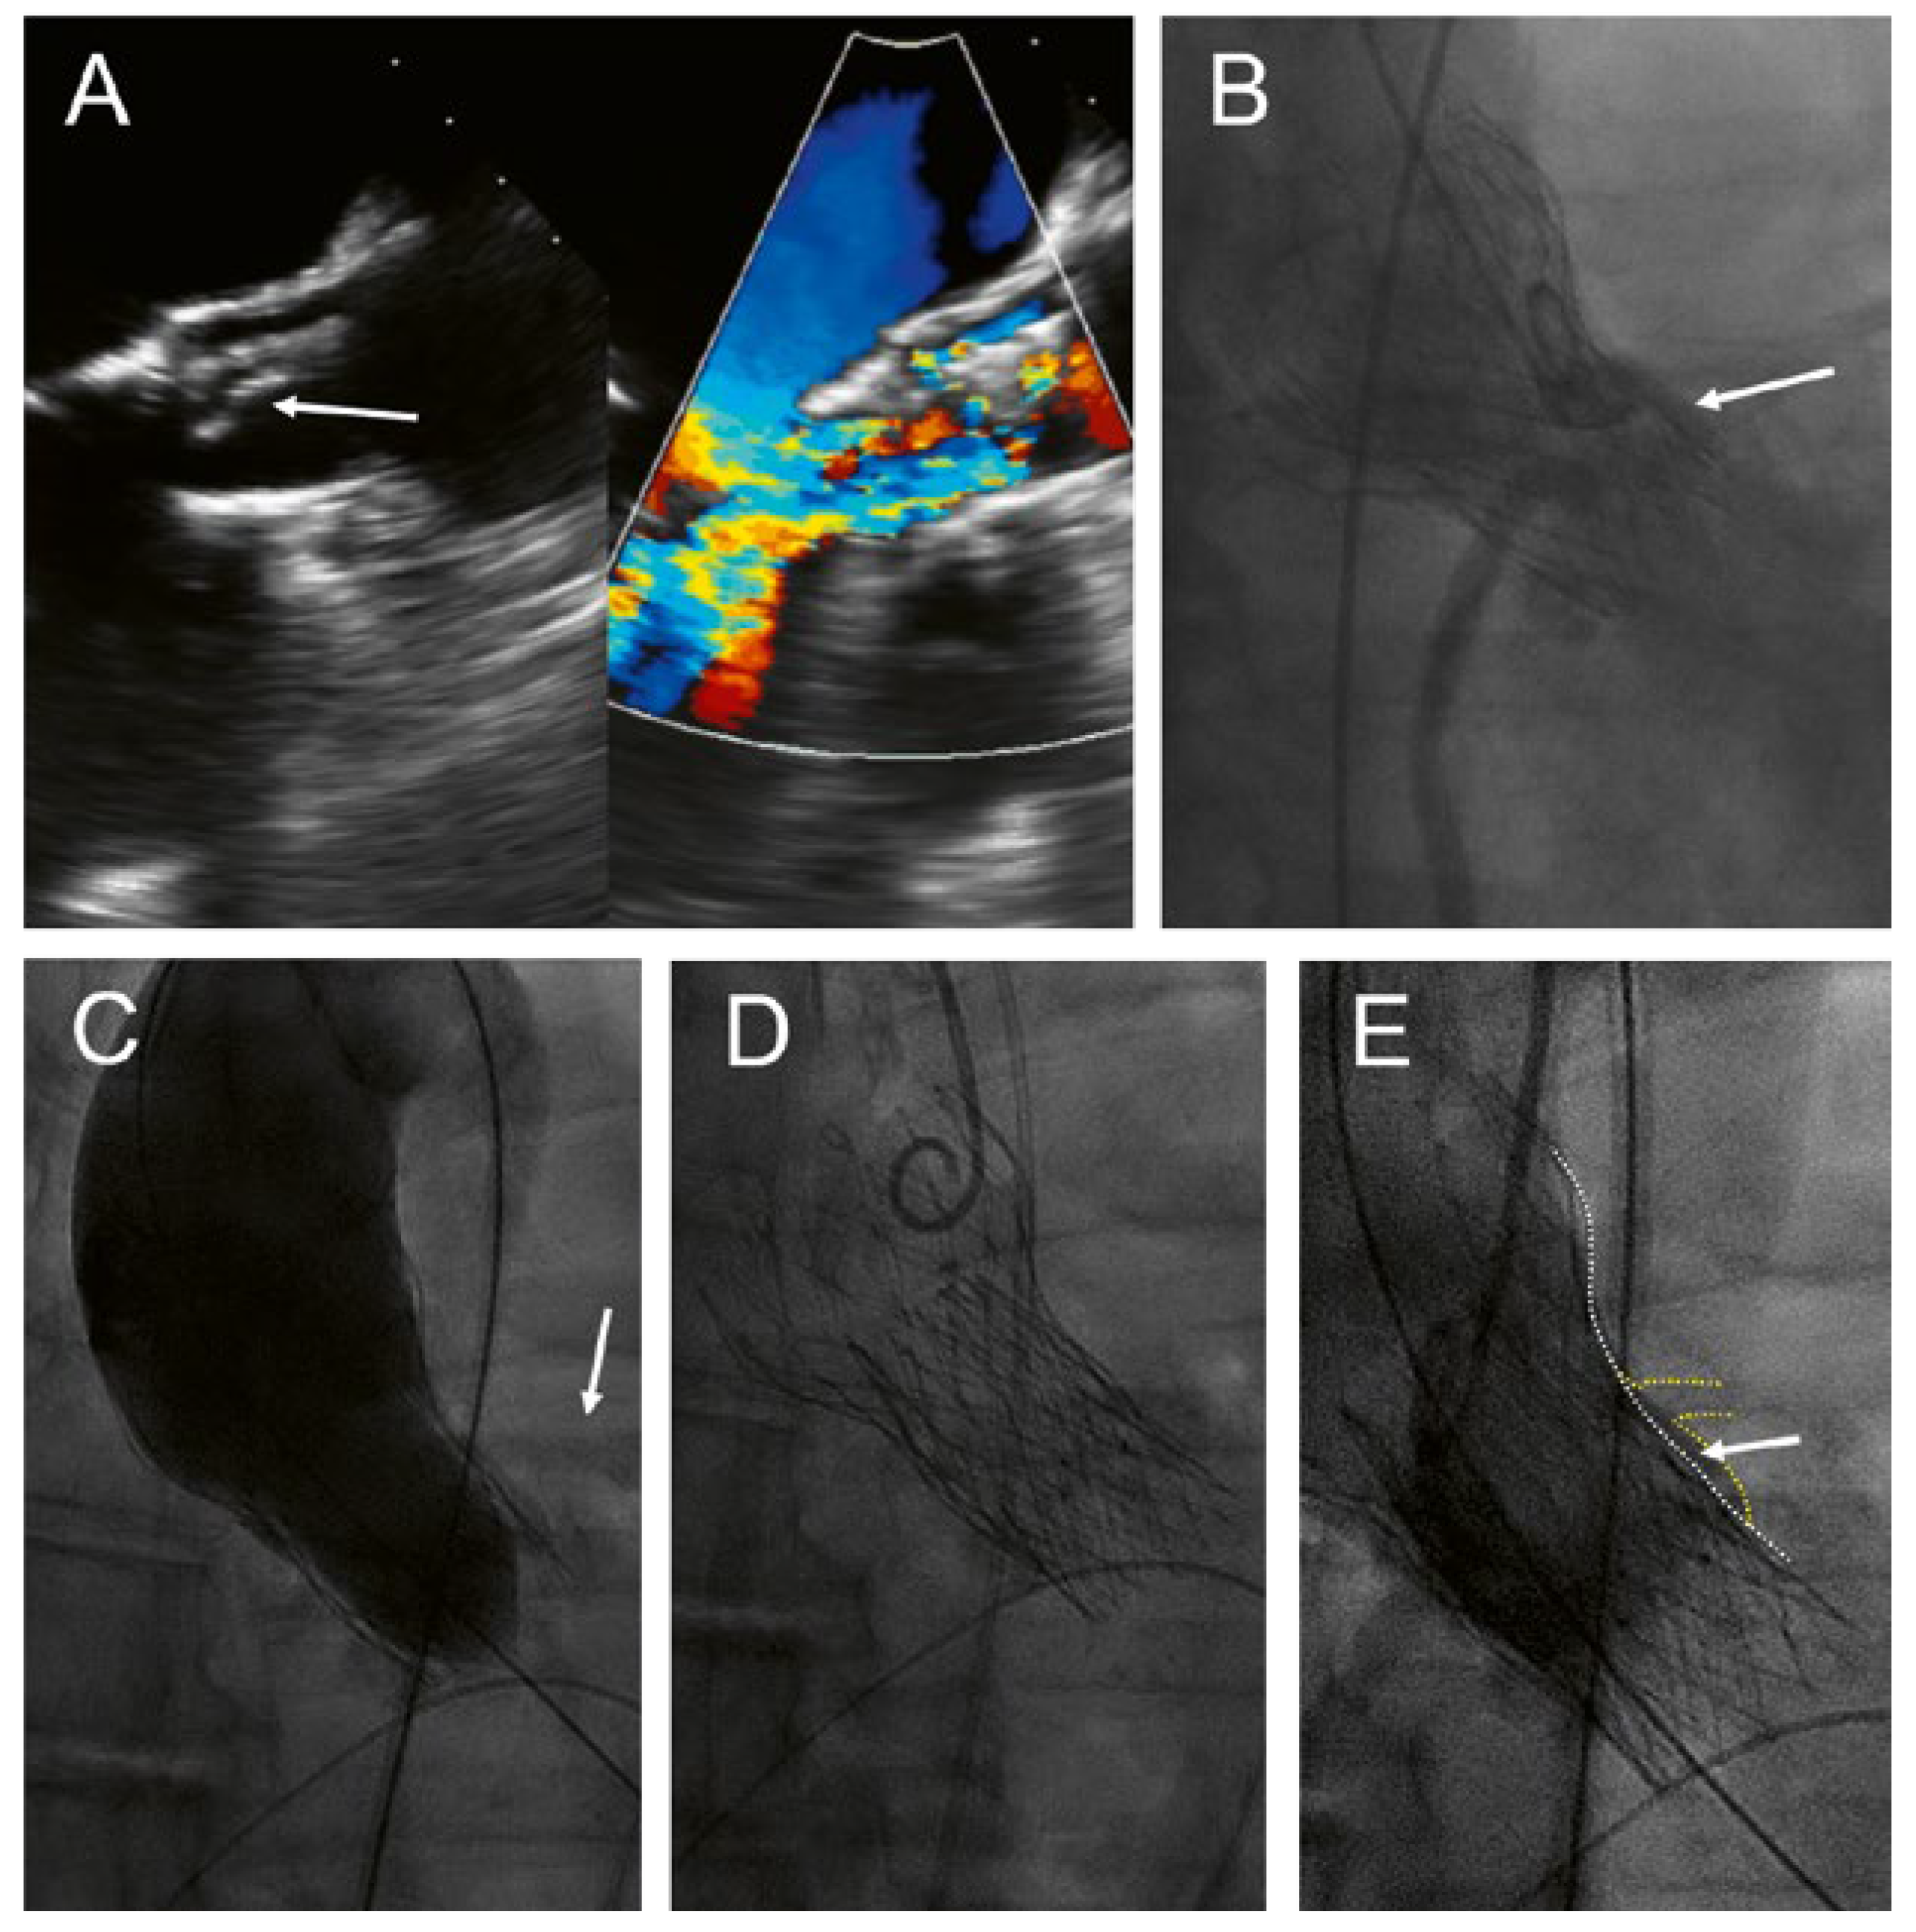

A 68-year-old man presented with increasing shortness of breath and a history of decompensated heart failure 8 years aher transfemoral implantation of a CoreValve 29 mm for severe, calcified aortic stenosis. Transthoracic and transoesophageal echocardiography revealed a partial tear-off and prolapse of one of the bioprosthetic leaflets of the CoreValve, with severe transvalvular and mild paravalvular regurgitation and a mild stenosis with a mean gradient of 26 mm Hg (Figure 1A). The patient’s main comorbidity was a congenital Laurence-Moon-Bardet-Biedl syndrome with blindness and obesity (body mass index 49 kg/m2). The patient was on rivaroxaban for persistent atrial fibrillation. Coronary angiography showed patent coronary arteries but a very shallow aortic sinus with a substantial risk of coronary obstruction (Figure 1B). In the presence of negative blood cultures and an unremarkable positron emission tomography (PET) scan, active endocarditis was very unlikely.

The patient was discussed in the interdisciplinary HeartTeam. The decision was to repeat the transcatheter aortic valve implantation with an Allegra transcatheter heart valve (THV) (NVT AG, Muri, Switzerland and NVT GmbH, Hechingen, Germany). Before implantation of the Allegra, a 22-mm TrueDilatation balloon was inflated and a supra-annular injection was performed to ensure patency of the coronary arteries (Figure 1C). Thereaher, an Allegra 27 mm was implanted about 6 mm below the inflow portion of the CoreValve (Figure 1D). Postdilatation was performed with the 22-mm TrueDilatation balloon. Postprocedural course was uneventful. Echocardiography before discharge showed a mild paravalvular leak and a mean gradient of 18 mm Hg; the calculated aortic valve area was 1.7 cm2.

Figure 1. Implantation of an Allegra valve in a degenerated CoreValve. This patient presented with severe transvalvular aortic regurgitation due to partial tear-off and prolapse of one of the leaflets (A, arrow). The aortic sinus was narrow with a high risk of coronary obstruction (B, arrow). An injection was performed during inflation of a 22 mm balloon to assess patency of the coronary arteries (C, arrow). Final position of the Allegra 6 mm below the inflow portion of the CoreValve (D), with only minimal space (E, arrow) between the frames of the transcatheter valves (E, white dotted line) and the sinus/left main coronary artery (E, yellow dotted line).